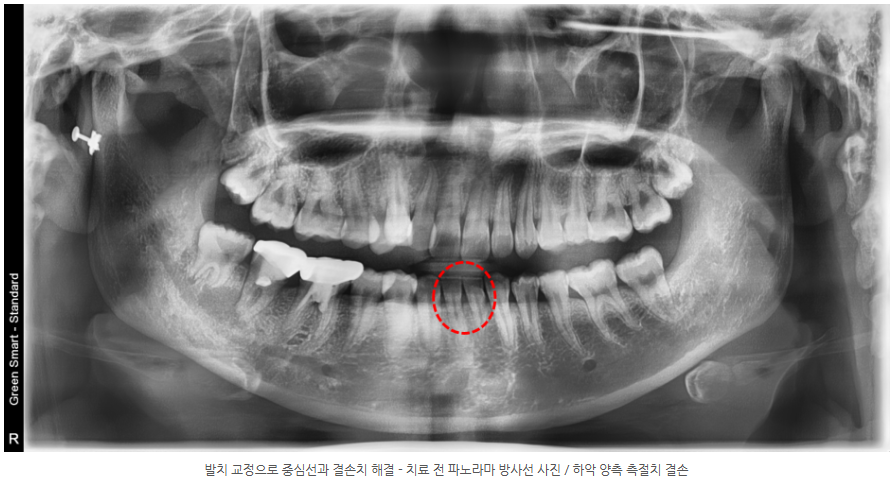

2025.12.24상악 총생과 중심선 편위, 하악 측절치 선천적 결손을 동반한 10대 여학생을

상악 소구치 발치교정으로 개선한 실제 사례. 교정 전문의의 진단과 치료 전략을 확인하세요.

하악 양측 측절치가 선천적으로 결손되어 견치와 제1소구치가 각각 측절치와 견치의 역할을 대신하고 있었습니다.

이로 인해 치아 크기·형태·기능의 부조화가 발생할 가능성이 높아, 교합 설계에 더욱 세심한 접근이 필요했습니다.